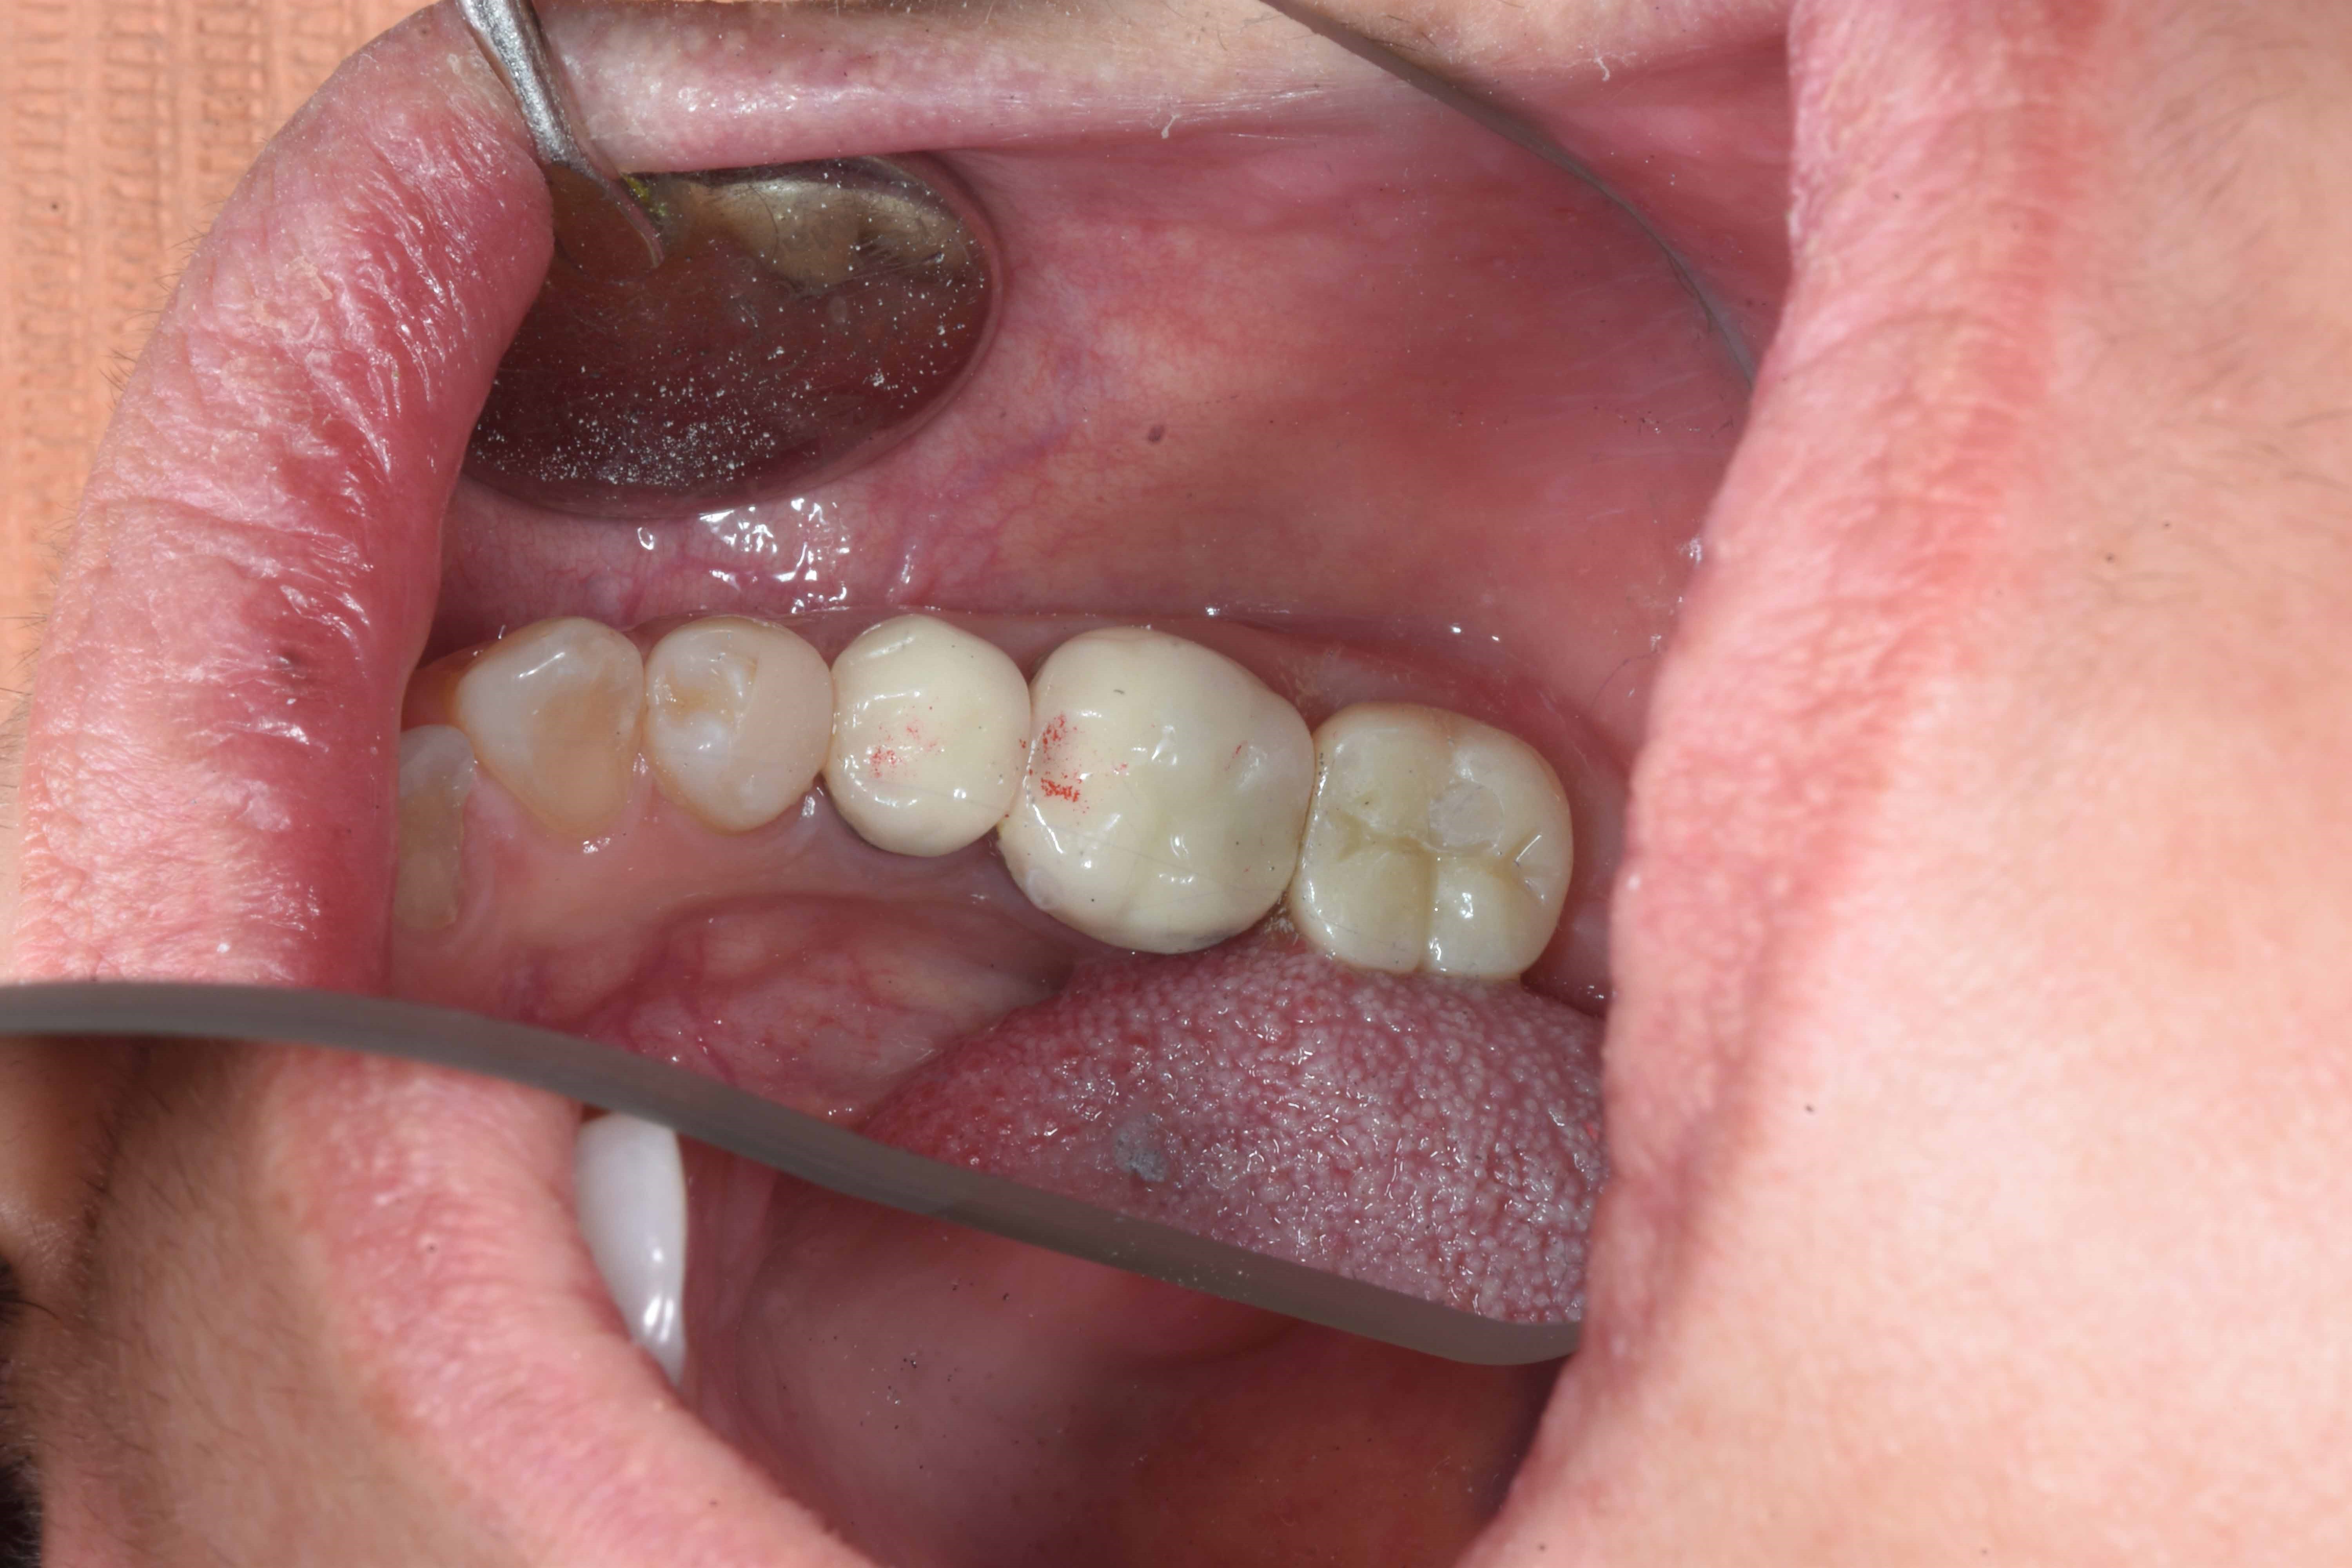

案例二

立即拔除壞牙根

當天完成植牙手術,並鎖上癒合螺帽

2-3月癒合,取下癒合螺帽,透過數位口掃至技公所製作假牙

7-10天完成假牙,試戴、調整咬合高度並鎖上,封填,完成